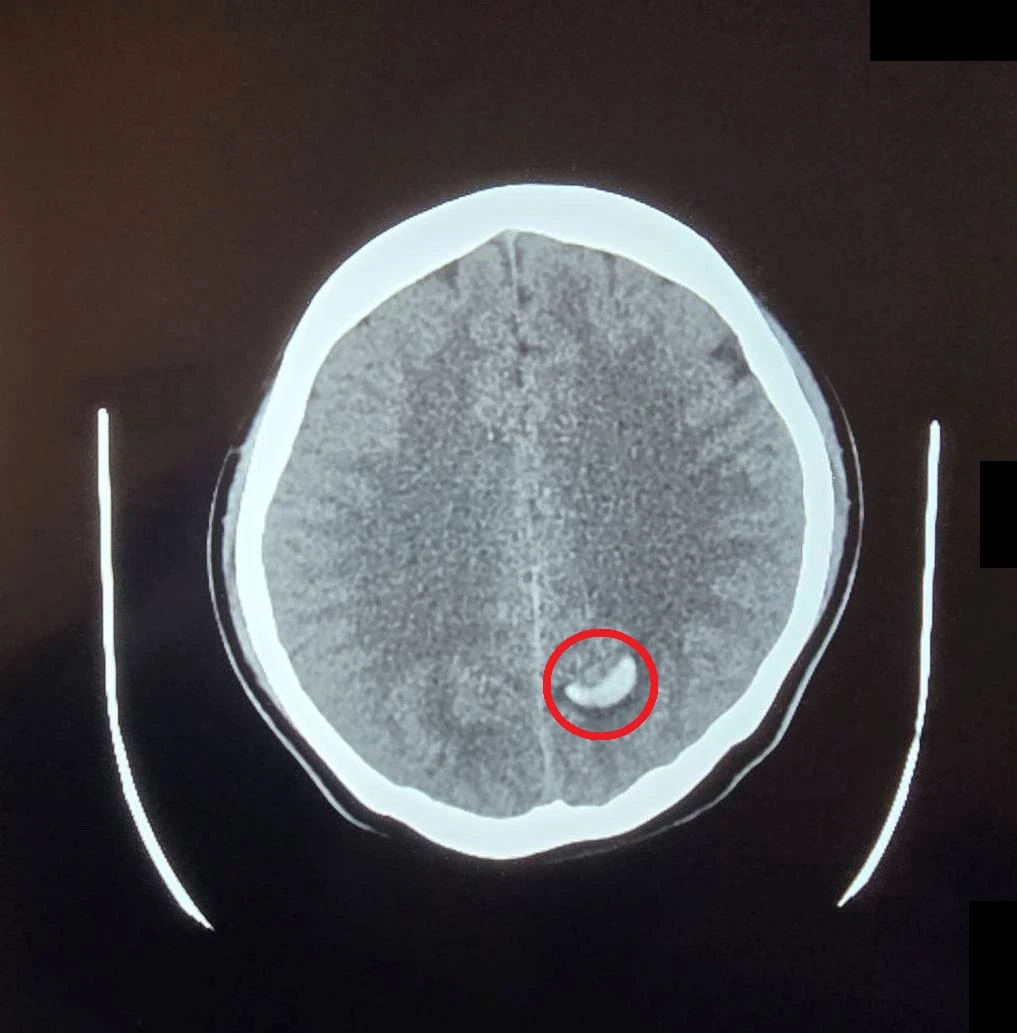

23歲的周小姐正值青春年華,卻在毫無預兆下感到一陣劇烈頭痛,隨即伴隨嚴重的頭暈與嘔吐感,家屬見狀趕緊將她送往大千綜合醫院急診。經腦部電腦斷層掃描,醫師赫然發現其左側腦部有出血跡象,且出血位置極其不尋常⋯⋯

病人經檢查發現左腦有出血跡象(紅圈處),且位置不尋常。(圖片來源:大千綜合醫院)